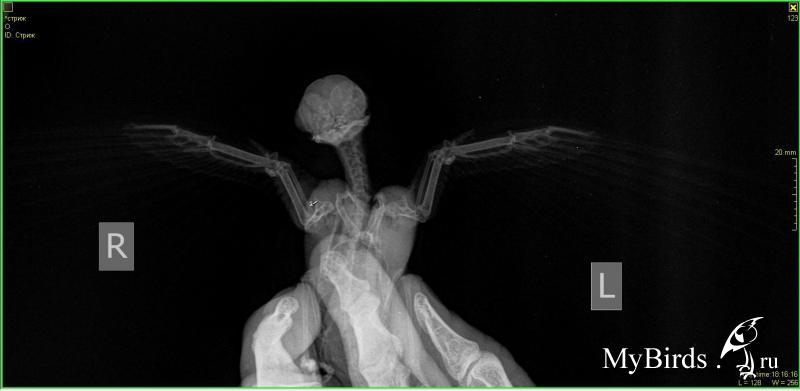

lilamor Опубликовано 25 июля, 2017 #1 Опубликовано 25 июля, 2017 Здравствуйте! Хочу спросить про этого стрижа. Он живет у моей знакомой. Привезли с переломом. Первый снимок (две фотографии) 30 мая, второй (тоже две) - 29 июня. Из лекарств она давала B1 и мелоксикам. Говорит, не может набрать высоту. Кормит сверчками и тараканами, чистит их как положено и тренирует его. "По распорядку - кормлю утром в 8:00 (примерно, бывает на выходных позже), вечером в 18:00ночью в 00:00 Тренировки - каждый день по буднях 1 раз вечером пускаю на накрытое покрывало, на выходных раза 3 в день.Перестал крылохлопить, когда сообразил, что внизу пол, а для него пол - это свобода))или висит на покрывале и не шелохнется. Если беру в ладошку- он слетает на покрывало, это единственный вариант тренировки для него, по-другому не получается. я его просто беру над ковром и над покрытым покрывалом слева (то есть покрывало закреплено на чем-то высоком у стены, спинки дивана, а к другой стороне оно опущено под углом). и держу - он начинает активничать и летит вниз на мягкое. Беру его всегда в перчатках! Хотя сначала не делала этого, о чем жалею( запылились немного перья, я периодически хлоргексидином прохожусь ватным диском."Вот тут видео как он летает https://vk.com/im?sel=26594438&z=video2...6a542ae99c5e316. Вопрос по снимкам: лучше или хуже стало? Что еще можно сделать? Есть надежда на полёт? Или он навсегда останется домашним питомцем?

Anysya Опубликовано 25 июля, 2017 #2 Опубликовано 25 июля, 2017 небольшая надежда у птицы была. так как смещение незначительное, хотя и перелом в очень плохом месте. т.е. результат был бы гадательным.шанс на успех был при условие полного покоя на полтора месяца. никакого обезбаливания - только боль заставляет сидеть спокойно первые две недели и кость встает на место, срастается идеально. мелоксикам в таком случае снижает шанс на подобный исход практически на 100%. а заставлять птицу тренироваться и летать с уже нарушенным сращиванием и недостаточной костной мозолью - именно для этого следующий месяц после первых двух недель - это просто издевательство. тем более, стриж и не нуждается в подобных тренировках и сам способен решить когда и как ему тренироваться.в общем, шансов на вылет практически не осталось. птицу жаль.